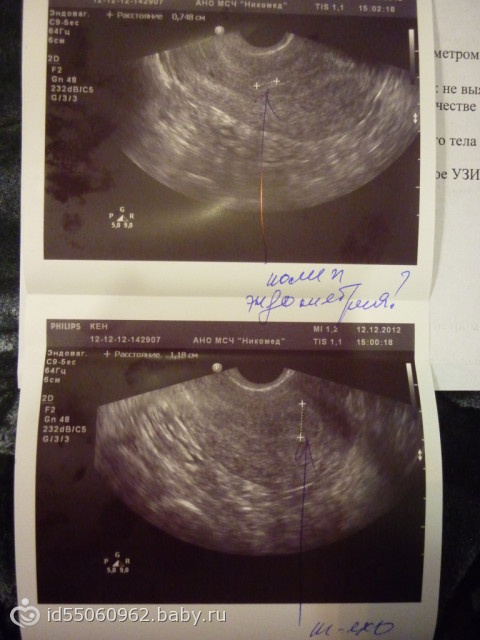

На экране аппарата врач УЗИ увидит неоднородное округлое образование. Появляется желтое тело в правом или левом яичнике в зависимости от локализации созревания доминантного фолликула и овуляторной яйцеклетки. Сторона созревания не имеет принципиального значения для будущей беременности и здоровья женщины.

Иногда опытный узист видит желтое тело в яичнике в другие периоды менструального цикла, например, во время задержки, когда предполагаемые менархе не начались в привычный срок. Это может свидетельствовать как о беременности, так и о гормональном сбое. Наличие желтого тела во время менструации не является 100% подтверждением того, что женщина вынашивает ребенка.

Кроме того, из желтого тела иногда развивается киста — полостное образование с жидкостью внутри. Патология характеризуется частыми сбоями в ежемесячном цикле, тянущими болями внизу живота. Более подробно в ситуации должен разбираться опытный гинеколог.